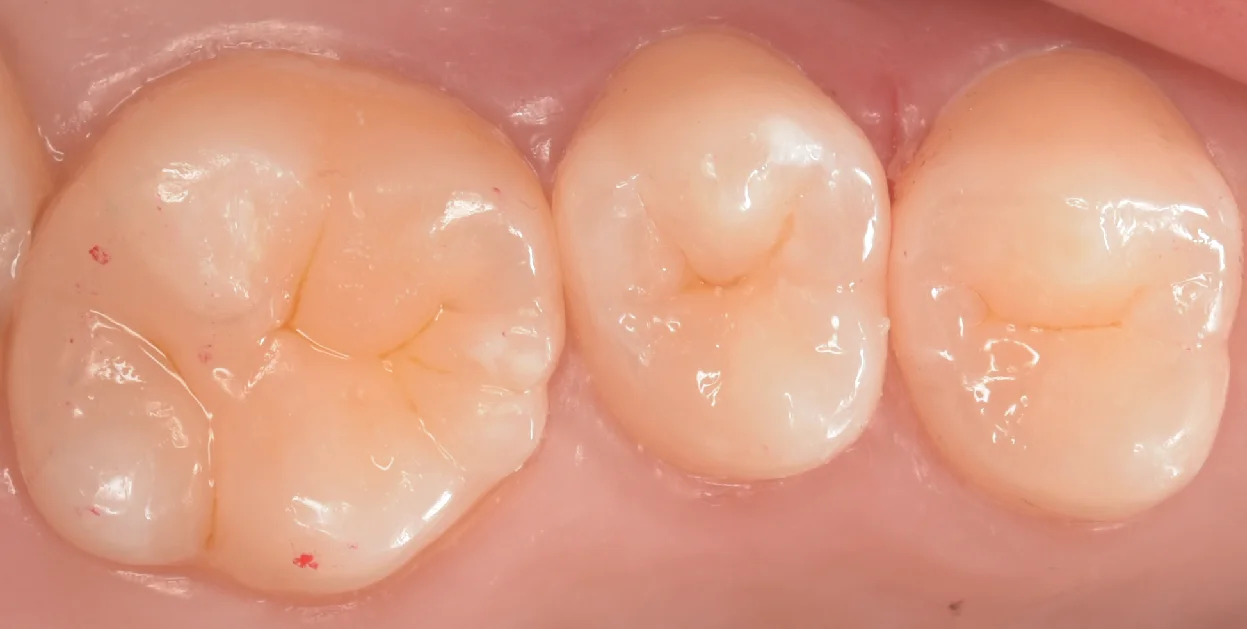

そして治療完了後の写真がこちらになります。

違和感なく綺麗に詰め終われたかと思います。

ダイレクトボンディングは歯科医師のみによって完結する治療法のため、術者による差が大きくなる治療法ですが、基本的には小さいむし歯ほどその難易度は下がり、精度は上がりやすくなってきます。